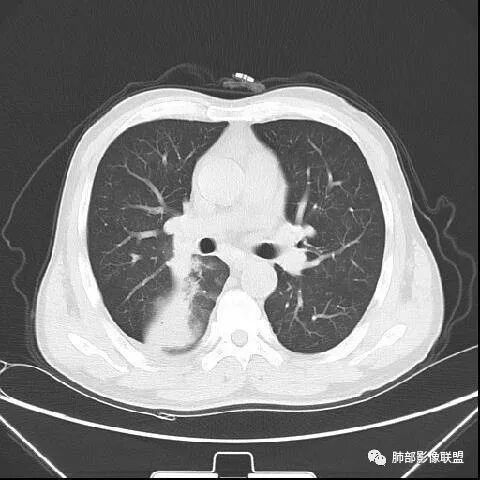

南边:紧贴着斜裂过来的一个病灶,它的特点是:外围大,内带小。它整个下叶背段体积与对侧相比稍微缩小一点,但是缩小地不是很厉害。外支朝前下走了,仔细看血管,肺动脉走行自然,直达远端。远端实变区是肉芽肿成分,稍微有一点低密度,没有明显坏死,稍微有一点点坏死。而且附近有很多卫星灶,附近很多斑片影,有一些明显有气道壁增厚,细支气管炎的特点,还有就是下叶其他段很多斑片状影。换个角度,第一如果是肺癌,刚才看到PET-CT提示肺癌伴阻塞性肺炎,这个是不符合的。第二如果是肺癌阻塞性肺炎,近端血管肺动脉走行不会那么自然集聚的,这个是不符合的。理由是:如果这个病灶是肺癌,那么明显属于中央型肺癌,中央型肺癌的特点是近端大,远端小,近端是一个肿块,远端阻塞,远端阻塞是阻塞性炎症或者不张,它应该体积缩小,斑片状实变,不会这么密实。刚才有老师提到支气管,这个片有缺陷的地方,给的图像好像那层,如果把其他图像拿开再重叠一下。

南边:这个肺门区,11区和7区都有一些淋巴结,淋巴结的形态不是类圆形,而是梭形的。这个病灶给的图比较少,个人倾向,第一强化非常均匀,肉芽肿性病变;第二,里面血管走行非常自然,远端大近端小,倾向炎性,特别是下面还有斑片状影,非阻塞远端,支气管远端病灶下叶背段,其他段也有,所以我倾向炎性;另外,它里面整个走行符合支气管树爬行征,我倾向结核可能,首先我定在炎性,其次有没有结核的可能。

鉴别诊断:肺炎性肺癌,胸膜下起源,外围大,局部占位效应,有膨隆有收缩,这个不太支持。支气管走行里面没有看到支气管进入很自然堵塞的粘液栓的特点。附近这些磨玻璃影,它的磨玻璃影要么边界清楚,要么由内朝外蔓延的,而不是沿着支气管束蔓延的。而且附近斑片状影,有些似乎有结节感,但是大部分不是,它不是我们常见的磨玻璃样结节,有些有,导致像腺泡样结节那种椭圆的沿着血管束分布的,我会把肺炎型肺癌放在待排。

右肺下叶背断肿块,外围大,内带相对狭长         远端有膨隆,边缘模糊、凹凸不平         血管走形自然,病灶近端支气管通畅,沿支气管树蔓延         周边有多发病灶,多为磨玻璃密度且边界不清。